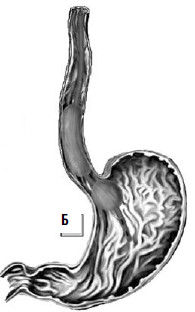

Уточнение источника кровотечения необходимо для целенаправленного применения возможных методов гемостаза. Известно, что при циррозе печени кровотечение может быть обусловлено: варикозно расширенными венами пищевода – 83 %, варикозно расширенными венами желудка – 10 %, синдромом Мэллори-Вейса – 4 %, язвой двенадцатиперстной кишки – 3 % наблюдений.

Для каждого вида кровотечения применяют свой метод гемостаза. Важно выбрать адекватный способ, поскольку второй попытки остановки кровотечения может и не представиться. Для определения источника кровотечения используют срочную фиброэзофаго-гастродуоденоскопию (ФЭГДС), во время которой подтверждают диагноз варикозного расширения вен пищевода, определяют зону нарушения целостности вены и интенсивность кровотечения. При умеренном кровотечении из варикозных вен пищевода, синдроме Мэллори-Вейса или язвы двенадцатиперстной кишки сразу может быть предпринята попытка его эндоскопической остановки. Наиболее эффективным методом остановки кровотечения из варикозных вен пищевода является их эндоскопическое лигирование. При этом эффективность метода достигает 90 %, а количество рецидивов составляет примерно 10 % (рис. 85).